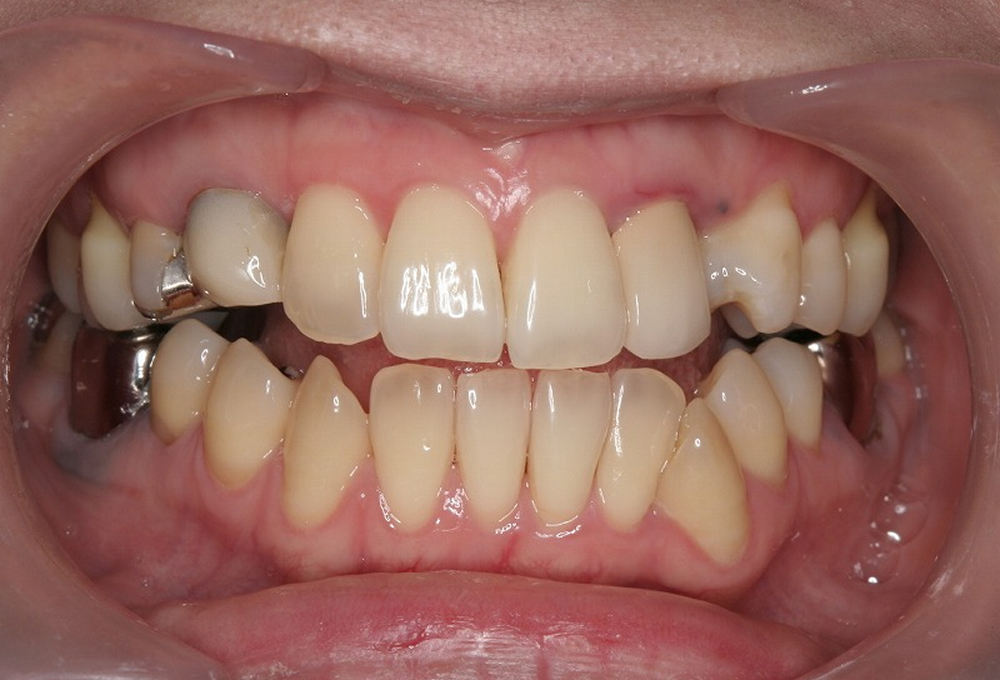

①術前

②矯正中